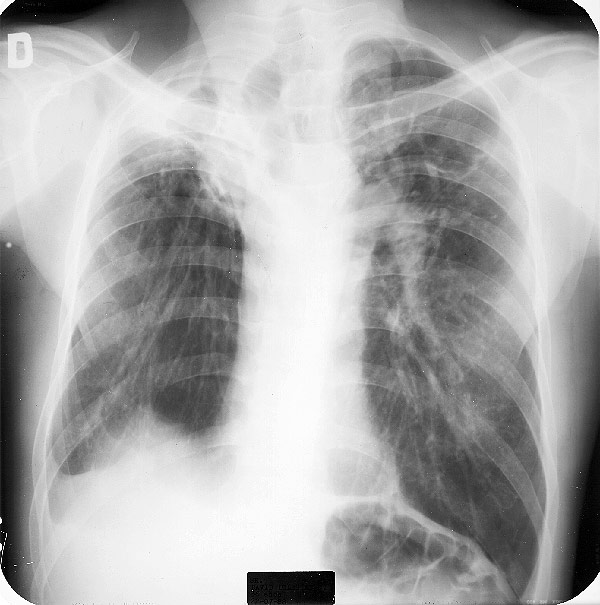

Otra causa de frecuente de opacidades pulmonares son las cicatrices de lesiones pulmonares con acumulación de tejido fibroso, usualmente retráctil. Su carácter residual no es siempre evidente por la sola radiología y suelen ser necesarios considerar el cuadro clínico del paciente, realizar otros exámenes o demostrar la estabilidad de la lesiones en sucesivos controles.

Examine la siguiente placa e indique sus alteraciones